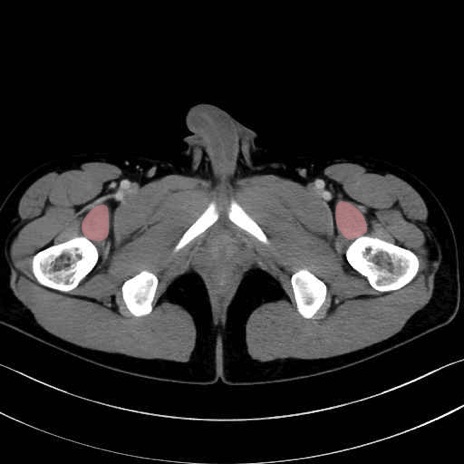

腸骨筋 (Iliacus)

大腿方形筋 (Quadratus femoris)